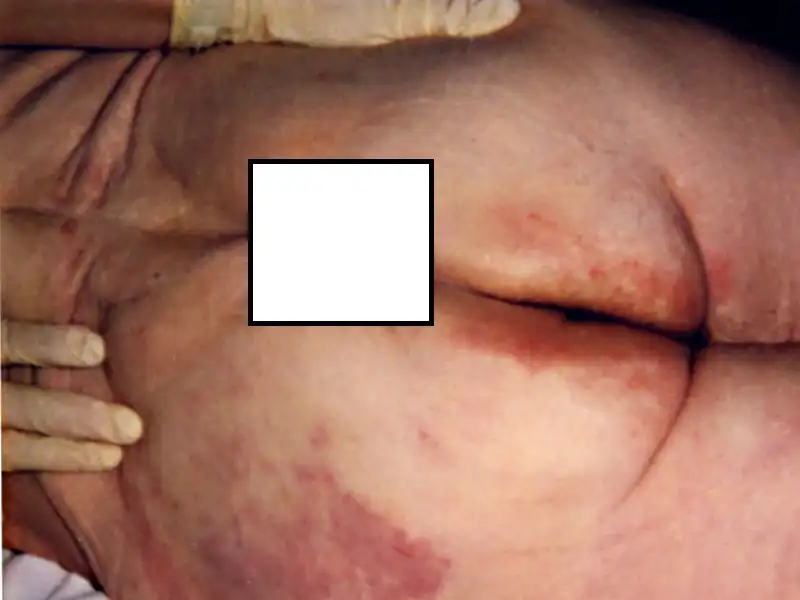

Пролежни и трофические язвы.

Lukum, нет, то что ты за обморожение принял - сухая гангрена при деабетической стопе.

а помоему тут нетолько пролежни....

- подборка кракодильщиков biggrin

Вот и мне подумалось, что тут и гангрены есть, помимо пролежней.